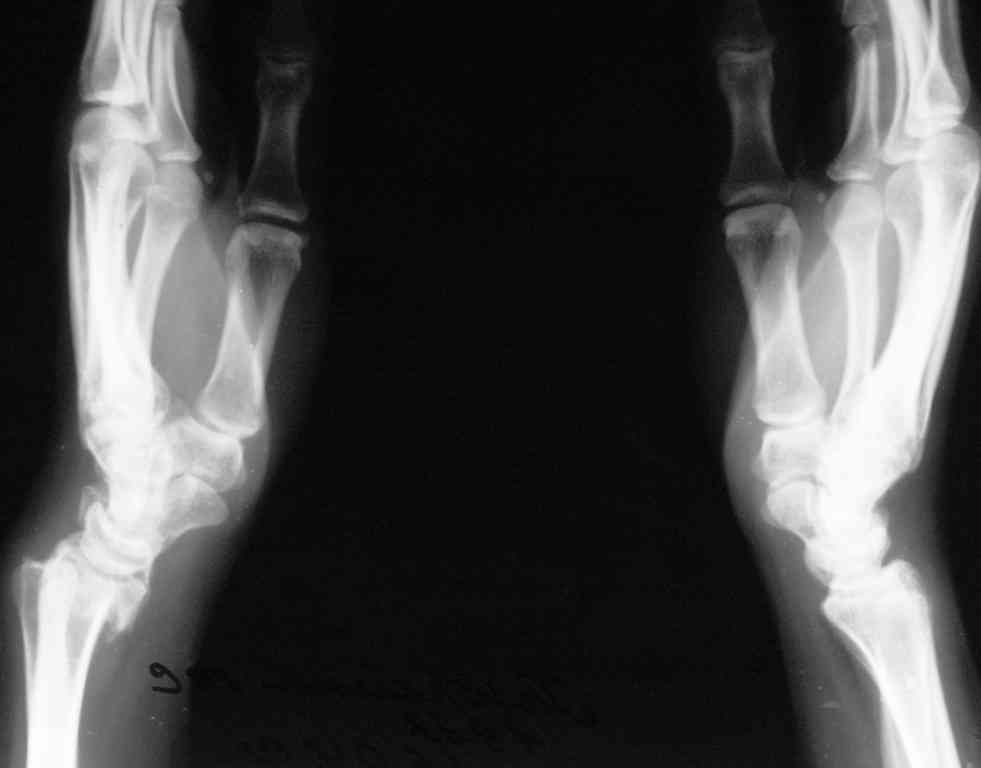

[Ortho] Последствия травмы предплечья

Спице-стержневой   аппарат   с  компактотомией  лучевой  кости,

костная  пластика  локтевой с  удалением  пластины. Не  комфортно,  но

больше  шансов  на  благоприятный  исход. Заканчиваю  лечение  с

похожей  деформацией  лучевой  кости.